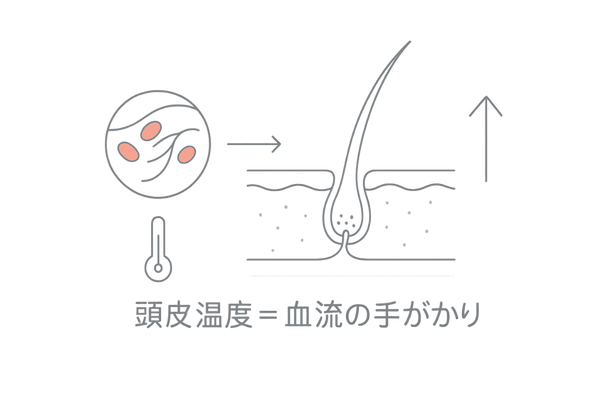

髪の毛は、毛根にある毛母細胞が細胞分裂を繰り返すことで成長します。この毛母細胞が活動するためには、血液によって運ばれる十分な栄養素と酸素が必要です。

つまり、頭皮の血行は髪の生命線ともいえます。頭皮の温度を測定することは、間接的に血流の状態を評価し、毛母細胞に栄養が適切に届いているかを知るための重要な手がかりとなります。

温度の異常は、血行の異常、ひいては髪の成長サイクルの乱れを示唆するサインなのです。

髪の主成分は「ケラチン」というタンパク質です。このケラチンは、食事から摂取したアミノ酸を元に、毛根の毛母細胞で合成されます。ビタミンやミネラルも、この合成を助ける重要な役割を果たします。

これらの栄養素はすべて、血液によって毛根まで運ばれます。また、細胞が活動するためのエネルギーを生み出すには酸素も重要です。

血行が悪くなるということは、これらの重要な栄養素と酸素の供給が滞ることを意味し、毛母細胞は髪を十分に作り出すことができなくなります。